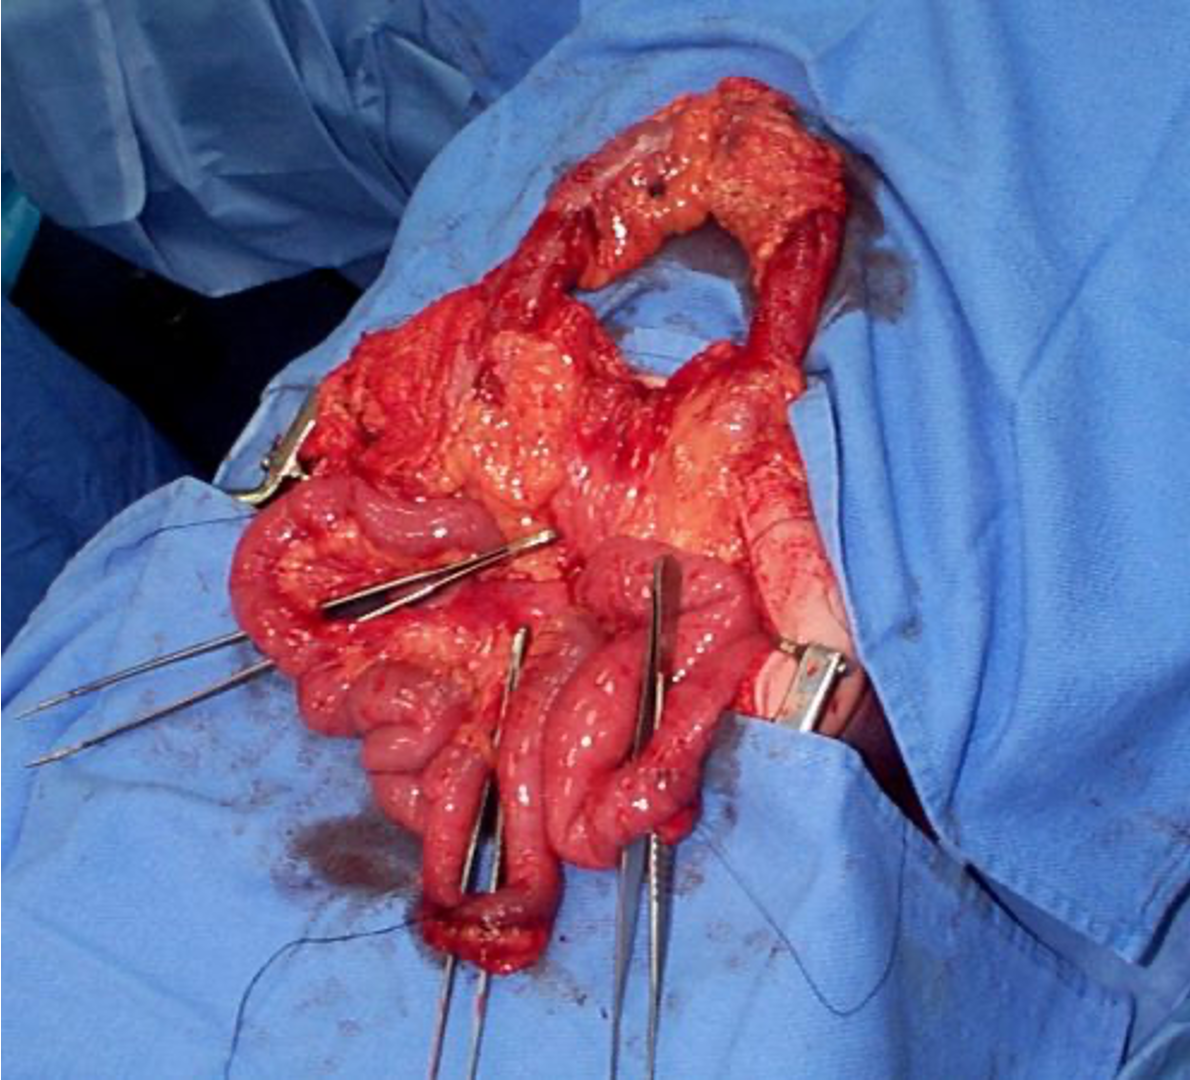

Definitive Tx

Ex-lap in the OR

Penetrating TraumaTreatment